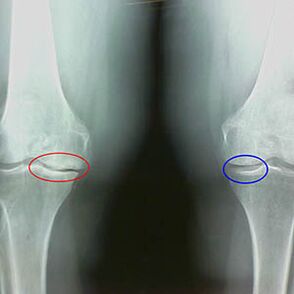

The first characteristics of X -rays of the second stage of knee osteoarthritis:

- The pointed edges of interminement tubers on the tibia, where the cross -shaped ligament is attached;

- narrowing of the joint gap on the medial side;

- The pointed edges of the condyles of the bones on the medial sides, less often in lateral - depending on the development of the valgus or the varial articular deformation.

For the second stage of LarsenThe narrowing of the joint deviation of more than 50% is characteristic, but this can only be verified in dynamics or comparison with a different seal.

The radiography shows the presence of osteophytes, a change in space between femoral bones and tibia, which indicates the loss of cartilage in the knee.Sometimes the X -ray of the knee joints shows significant signs of cartilage wear, but patients do not feel significant pain.On the contrary, osteoarthritis of the first step can disturb the knee function, since the cause of pain is the hypotonic muscles.